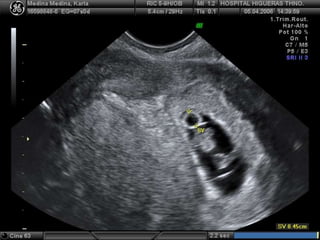

 Frecuencia cardiacadebe ser detectada cuando embrión alcanza 4 a 5 mm  Visualización de actividad cardiaca a la 8 semana es signo de buen pronóstico, la tasa de pérdidas del embarazo es de 2 al 3%  Bradicardia embrionaria es muy mal pronóstico  Latidos cardiacos en primer trimestre 90 128 174 161 147 6ª 6+4 9ª 11ª 14ª